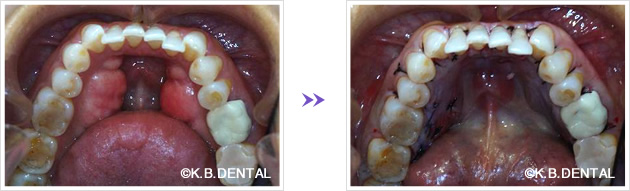

下顎骨隆起除去 症例2(下顎舌側両側骨隆起)

下顎の舌側に発生した骨隆起です。手術時間は約2時間で、静脈麻酔下で除去します。

下顎骨隆起除去 症例3(下顎舌側両側骨隆起)